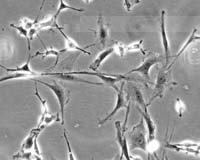

To do this, scientists generated a specific type of astrocyte support cell from the GRPs, which were discovered by cell biologist Margot Mayer-Proschel of the University of Rochester Medical Center.

Rats given this specialized astrocyte cell formed less scar tissue and nerve damage, as opposed to the control group that was transplanted with un-cultured cells. Their locomotion also improved to the point where they could walk completely normally up to two weeks after receiving the treatment.